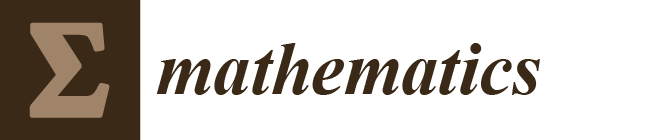

3. Main Geometrical Characteristics of Aorta